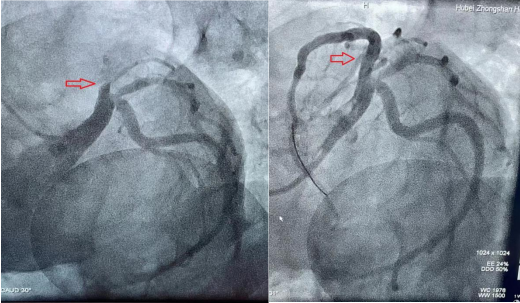

血管开通前 血管开通后

在患者家属手术签字后,心血管内科介入导管室启动,介入团队成员在20分钟内就到达导管室,并做好术前准备。患者被送入导管室,6分钟完成心血管冠脉造影,发现导致雷先生发病的前降支血管已完全闭塞了,此时雷先生真的是命悬一“管”啊。在征得家属同意后,心血管内科副主任李昌仅用5分钟左右的时间就开通了雷先生的“罪犯”血管,给雷先生开启了一条生命通道。一场争分夺秒的生死赛跑终于结束,雷先生的命保住了。此时,从雷先生进91porn 大门到血管开通仅仅才过去一个多小时,时间就是心肌,时间就是生命!